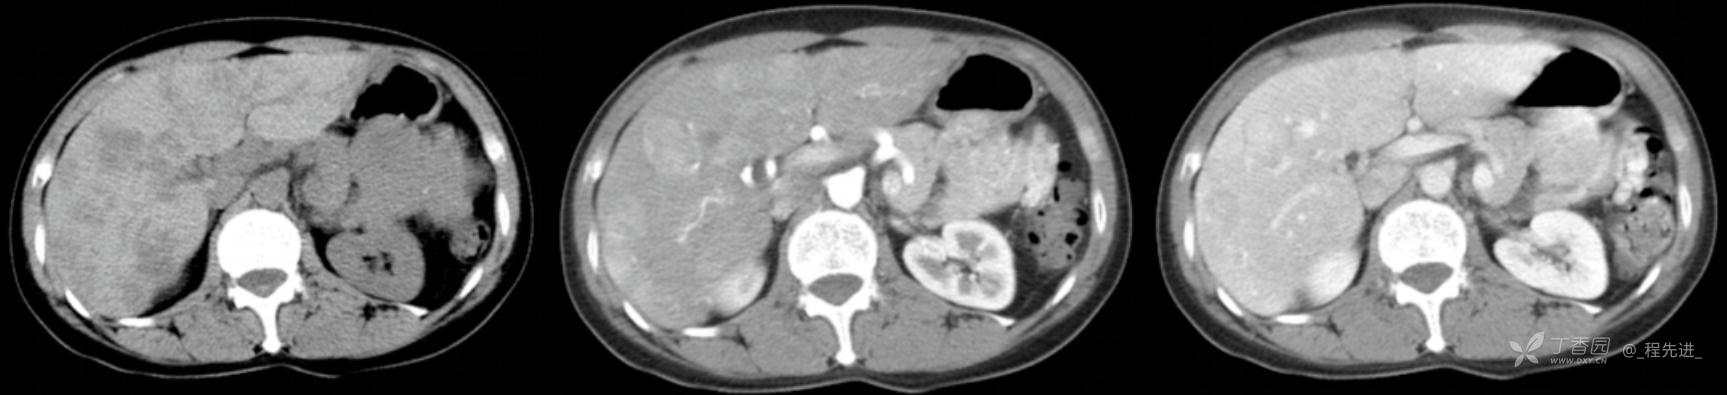

图像左边为平扫,中间的是动脉期,右边的是静脉期